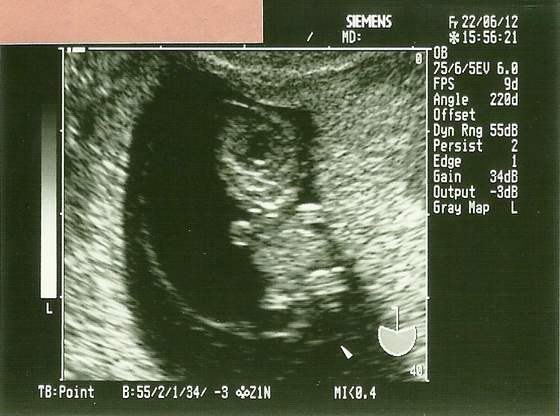

skanowanie0001.jpgskanowanie0003.jpg

Nooo to mój maluch :) 9 tydzień z haczkiem. Teraz wizyta 10 go i będzie równiśki 12 tydzień i genetyczne badanko :)